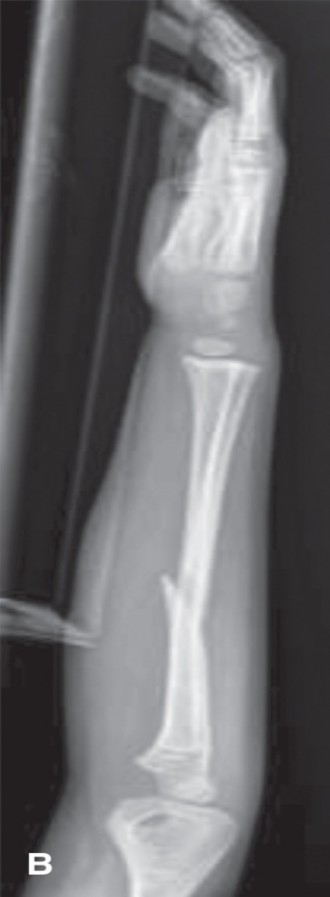

Complete Distal Forearm Fracture

- Radiographic Findings: AP and lateral radiographs of the right forearm and wrist revealed a complete, significantly displaced, and angulated transverse fracture of the distal metaphysis of the radius, approximately 2.5 cm proximal to the physis. There was substantial dorsal displacement of the distal fragment, with approximately 35 degrees of apex volar angulation. The distal ulna also demonstrated a transverse fracture through its metaphysis, with minimal displacement but significant shortening relative to the radius.

- Classification: Complete, displaced distal radius and ulna metaphyseal fractures.

- Decision: Closed reduction and long arm casting.

- Rationale: The significant dorsal displacement and apex volar angulation (35 degrees) exceeded acceptable limits for a 10-year-old. While remodeling potential exists, a malunion of this magnitude could lead to functional deficits and cosmetic deformity. A stable closed reduction, followed by immobilization in a long arm cast, was indicated to correct the deformity and allow for healing in an acceptable position. Unstable reductions, inability to achieve acceptable alignment, or persistent neurovascular compromise after reduction would necessitate operative intervention (e.g., CRPP or ORIF).